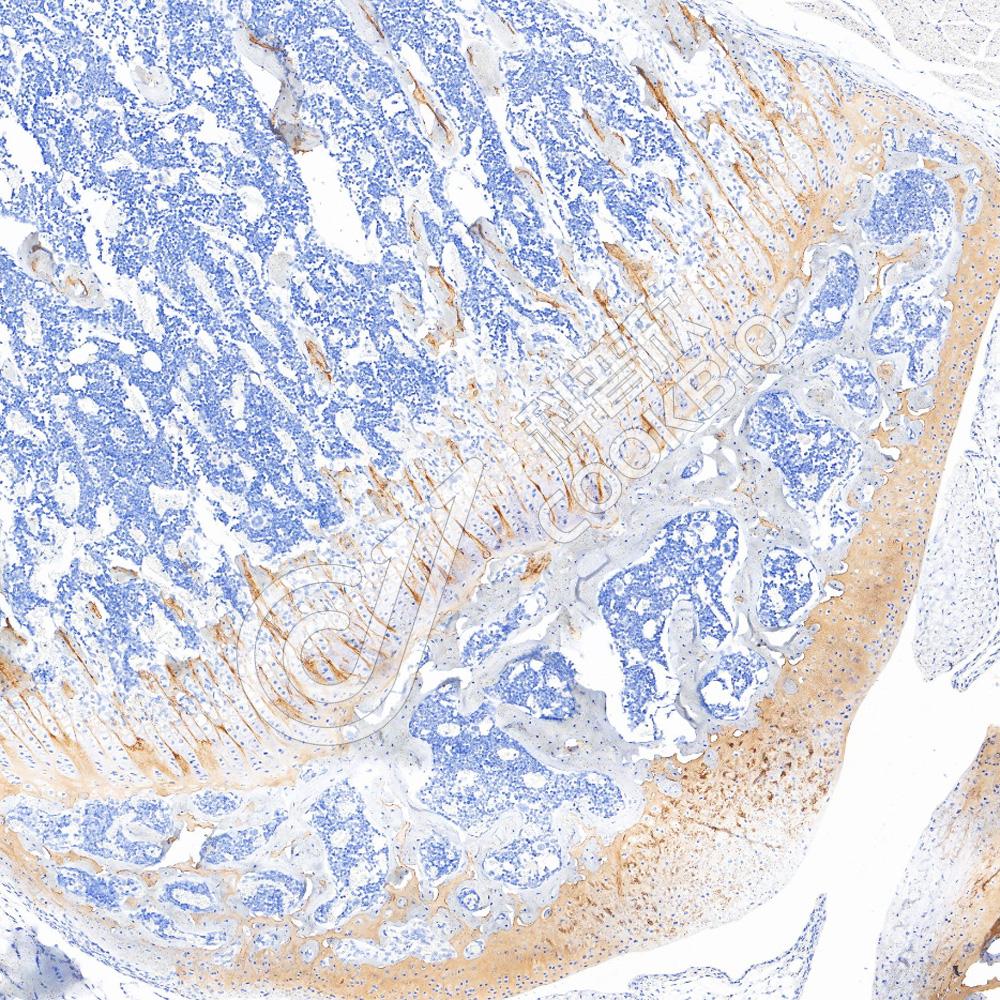

IHC检测p40-DeltaNp63蛋白(货号 K5450009).

样品: 人食管癌, 4%多聚甲醛 (货号KSG1101) 固定12-24小时.

抗原修复: 柠檬酸抗原修复液(干粉, pH 6.0) (KSG1201), 高压锅均匀喷气计时2分钟.

—抗: 1: 1300稀释, 4℃ 孵育过夜.

二抗: S-vision免疫组化多聚二抗(山羊抗兔),即用型 (货号KB3906), 室温孵育20分钟.